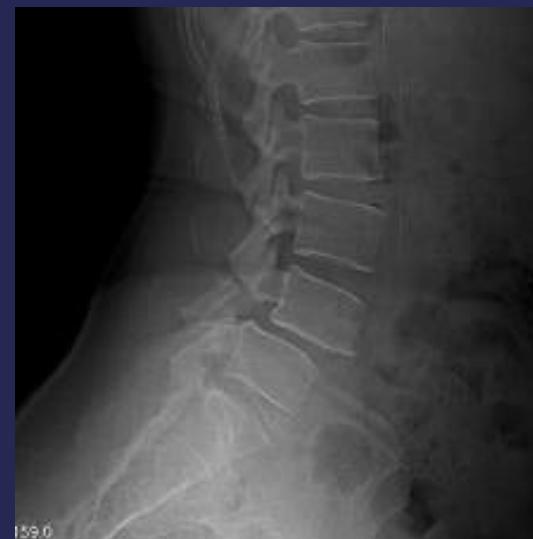

Radiographic Findings

- Narrowing of disc space

- Marginal bony spurs (Osteophytes)

- Osteoarthritic changes in facet joints